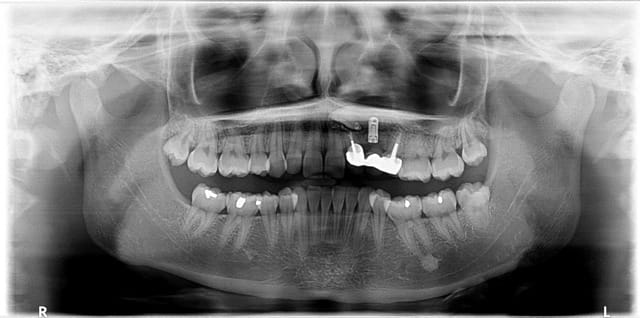

Découvert fortuitement lors d'un contrôle.

La patiente à moins de 25 ans. Le travail a environ 10 ans... Petite mobilité sur le bridge. Je vous laisse imaginer la chronologie des événements.

la 22 semble perdue et il faudra vraisemblablement extraire la canine incluse (et donc virer l'implant...) pour pouvoir gérer la suite...

ROG ou greffe ensuite et 2 implants et 22/23 ou 22/24 si la 24 n'est pas conservable...

là où je suis le plus étonné...c'est patiente de moins de 25 ans et travail de 10 ans...faire çà a une gamine de 15 ans, çà me paraît surréaliste...

Très beau cas clinique pour montrer pourquoi il ne faut pas faire d'implant et encore moins d'implant solidarisé a des dents naturel chez un patient qui n'a pas fini sa croissance.

L'implant est ankylosé donc toutes les dents du bridge se comporte comme si elle était ankylosé. La croissance vertical n'étant pas fini les trois dents du bridges sont resté sur place quand tout les autres dents on continué a égresser en emenant l'os alvéolaire avec eux.

Résultat des courses le bridge se retrouve en infraclussion, la valeur des piliers prothétique est considérablement affaibli car le rapport couronne racine ne sera pas favorable, de plus l'esthétique peut etre compromis du fait du bas niveau de l'os alvéolaire, probablement que la gencive est trop basse aussi.

Une solution : faire une egression de 22 et 24 pour recréer le volume osseux qui aurait normalement dut se former durant la croissance, meme si les piliers ne sont pas conservable le rendu esthètique des implants sera amélioré. Au passage on peut aussi recréer l'os de 23. Une fois egresser les piliers devrais pouvoir etre conservé quelque année, le rapport couronne racines devenant plus favorable.

Ps : le stomato n'aurait pas essayer de tracter la canine? On semble voir une attache sur la couronne.

oui, c'est un implant "fantôme"...posé, jamais utilisé!!!

et le truc sur la couronne de la canine amha c'est plus un dépassement de pâte endo...

Dans le dossier, l'implant était douloureux en décembre et ligne suivante en mai : endo 22 et 24...